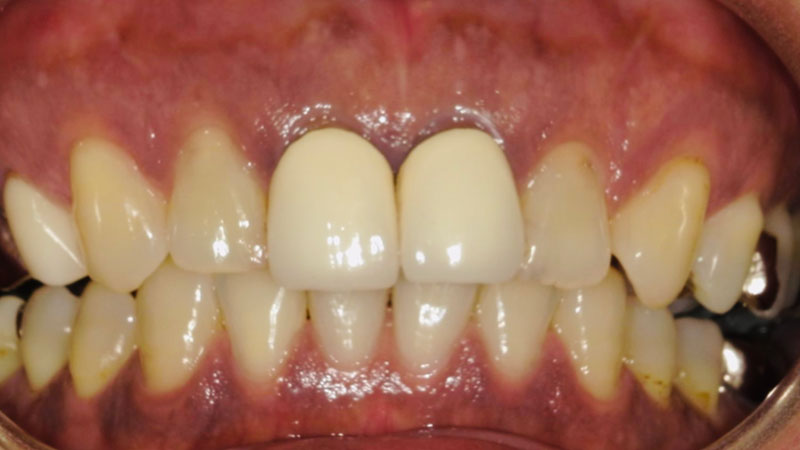

セラミックブリッジによる前歯の審美回復

噛み合わせによって右上2が動揺していた患者さまです。

歯周基本治療を行い経過を観察していましたが、状態の改善が見られず抜歯を決断されました。

治療の選択肢を丁寧にご説明した上で、今回はセラミックブリッジを選択。

抜歯と同時に仮歯を装着し、傷の治癒を待ってからセラミックの型取りを行いました。

また、この患者さまは噛み合わせによって時間破折やすり減りが起こり審美的な面も気にされていましたが、最終的には正常な歯並びに整えることができました。

見た目の自然さとしっかり噛める機能を両立し、大変ご満足いただいています。

| 患者様 | 50代男性 |

|---|---|

| 主訴 | 前歯が欠けた |

| 治療費 | ジルコニアセラミック費用:1歯132,000円(税込) ジルコニアブリッジ6歯総費用:726,000円(税込) |

| 治療期間 | 2ヶ月 通院回数:約5回 |